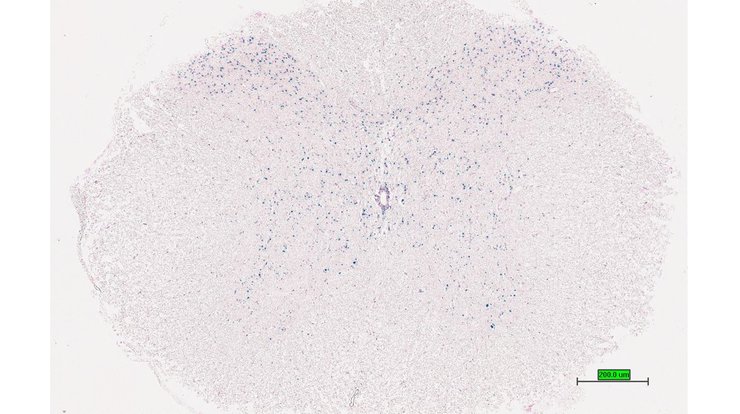

TS28: spleen Present UC Davis_1880927

TS28: spleen Present UC Davis_1880928

TS28: spleen Present UC Davis_1880929

TS28: spleen Present UC Davis_1881003